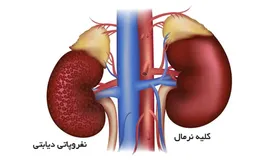

استفاده بیرویه از داروهای گیاهی، به ویژه گزنه، میتواند به کلیه بیماران دیابتی آسیب جبرانناپذیر وارد کند.